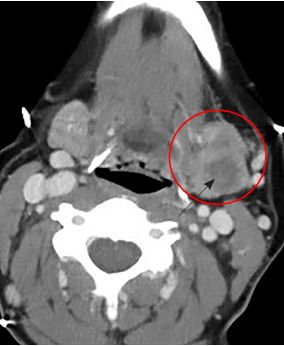

La TC o la RNM deben reservarse para los casos en que el diagnóstico de parotiditis recidivante ofrezca dudas, o ante la presencia de otros procesos patológicos, para los cuales son más confiables.

El diagnóstico se realiza sobre bases clínicas y puede confirmarse con la ecografía, en algunos casos suplementarse con sialografía o tomografía computarizada (TC) o resonancia nuclear magnética (RNM).